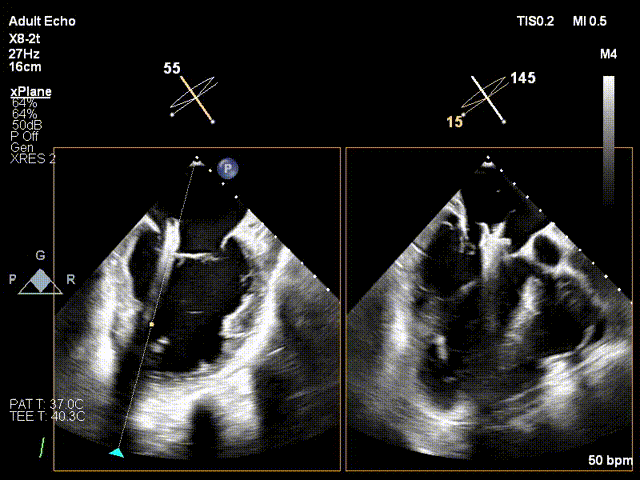

1. 术中基线评估三尖瓣反流程度

术中基线